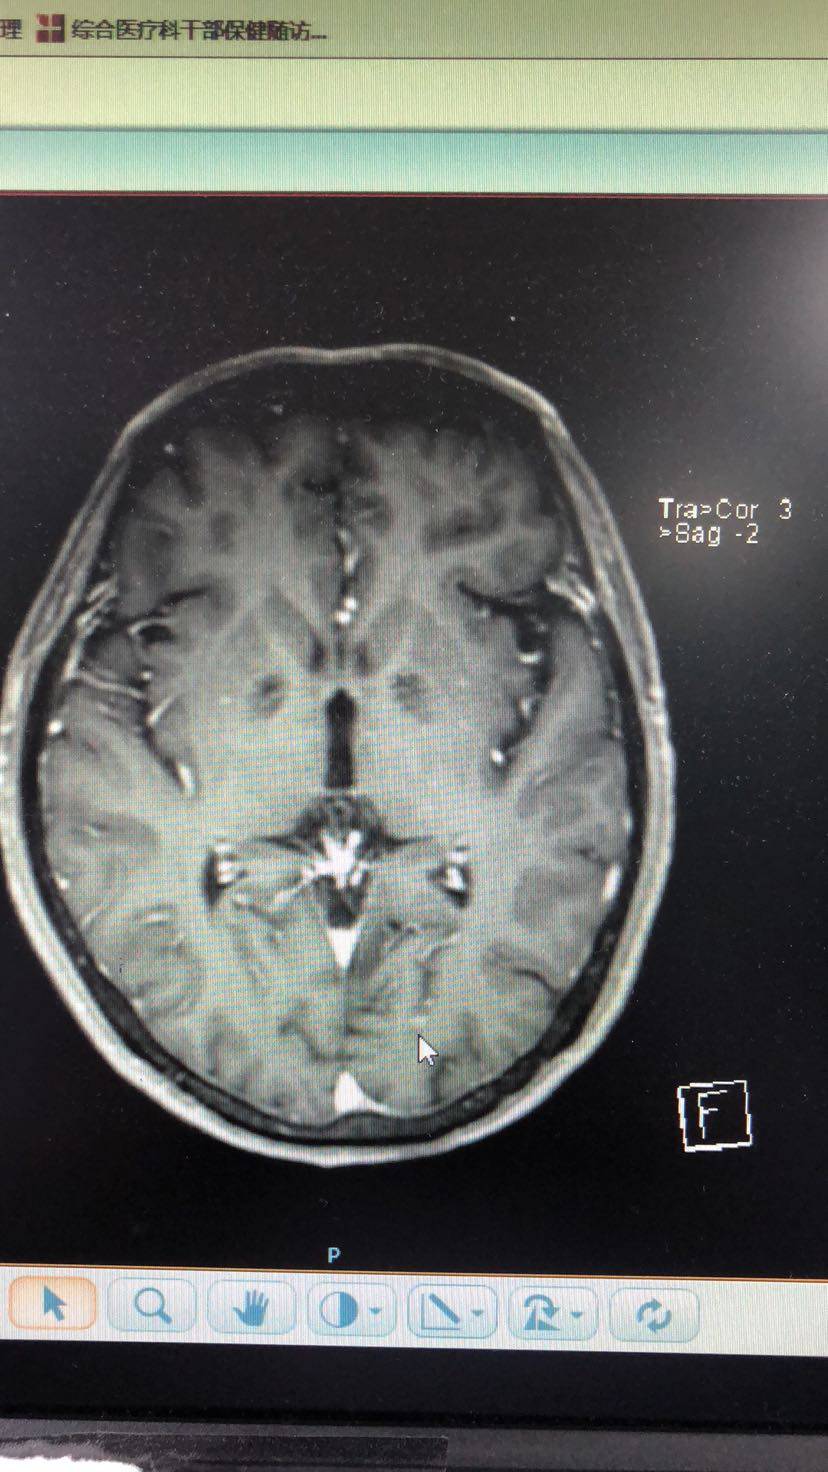

肺鳞癌术后半年怀疑脑转移,哭过之后擦干眼泪继续战斗。求教觅友们,脑部放疗采用哪种方式好?射波刀、伽玛刀、还有立体定向放疗,哪种更好?目前我爸没有脑转症状,一个结节4mm、一个结节2mm,医生建议观察一个月,如果增大就放疗;如果没有变化就继续观察。另外,无基因突变盲试靶向药是选择特罗凯还是9291?我知道阿法替尼是指南规定的鳞癌用药,但阿法替尼入脑效果不好,没用。我家pd-L1表达65%,目前由于放射性肺炎的存在暂时不考虑上pd1。此次脑部放疗后如何预防下一次的脑部复发呢?毕竟放疗治标不治本。另外,求有经验的觅友帮忙看一下脑部核磁影像,看一下鼠标指出的地方是否确为转移瘤。叩谢各位觅友了。